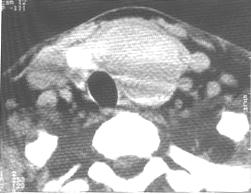

左侧甲状腺腺瘤。CT平扫示左侧甲状腺下极可见一软组织肿块,其内密度较均匀,未见明显钙化,边缘光滑锐利,周边可见低密度环。气管受压向右后偏移。 | |

CT表现: 1.甲状腺内单发或多发,圆形或类圆形结节,密度多为均匀,低于正常甲状腺,囊性变多见。 2.病变一般大小在1-6cm左右,边缘光滑锐利,肿块有完整包膜,病灶与正常甲状腺组织分界清楚,但与周围器官无浸润,病灶可有沙粒样钙化。 3.增强扫描可强化。实性为均匀结节状强化,囊变者呈环状强化,囊变区不强化。 |